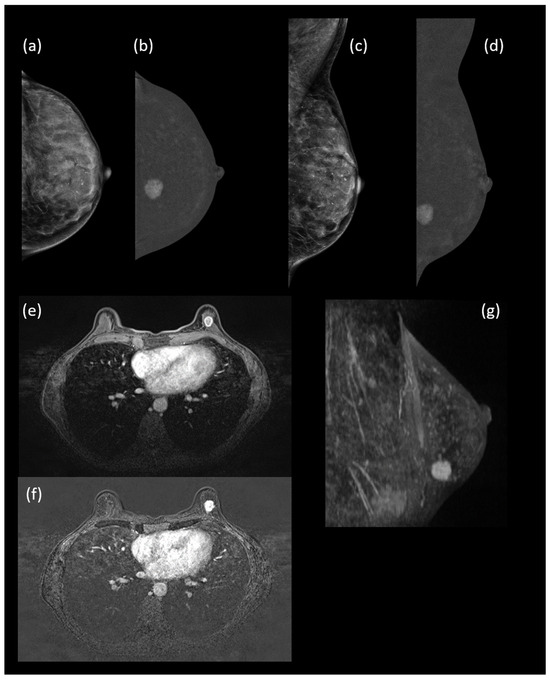

Background/Objectives: Surveillance of women at increased risk for breast cancer requires high-sensitivity imaging. This study compared contrast-enhanced mammography (CEM) with low-energy CEM (LE-CEM) and breast MRI in this population. Methods: This retrospective analysis included 461 women enrolled in a high-risk imaging [...] Read more.

Background/Objectives: Surveillance of women at increased risk for breast cancer requires high-sensitivity imaging. This study compared contrast-enhanced mammography (CEM) with low-energy CEM (LE-CEM) and breast MRI in this population. Methods: This retrospective analysis included 461 women enrolled in a high-risk imaging protocol (March 2019–October 2022). Lifetime breast cancer risk was estimated using the Tyrer–Cuzick model. All participants underwent CEM and breast MRI ≥ 72 h apart. LE-CEM images were used as a surrogate for digital mammography. Four readers independently interpreted LE-CEM and CEM; a separate group of four readers interpreted MRI. Diagnostic performance was assessed using sensitivity, specificity, and area under the receiver operating characteristic curve (AUC) within a multireader, multicase framework. Noninferiority testing was performed with Δ = 0.05. Mean glandular dose (MGD) for CEM was recorded. Results: CEM showed higher sensitivity than LE-CEM (83.0% vs. 68.9%, p < 0.001) with similar specificity (90.8% vs. 92.5%, p = 0.176). Mean AUC increased from 0.856 for LE-CEM to 0.936 for CEM (p < 0.001). CEM and MRI showed comparable sensitivity (82.9% vs. 86.1%, p = 0.547), specificity (90.8% vs. 86.5%, p = 0.318), and mean AUC (0.936 vs. 0.933; p = 0.839), confirming noninferiority of CEM. MGD per view ranged from 1.56 to 3.10 mGy. Conclusions: Contrast-enhanced mammography provides diagnostic accuracy equivalent to breast MRI and superior to LE-CEM, with acceptable radiation dose, supporting its use for surveillance in women at increased breast cancer risk. Full article

Show Figures

Figure 1